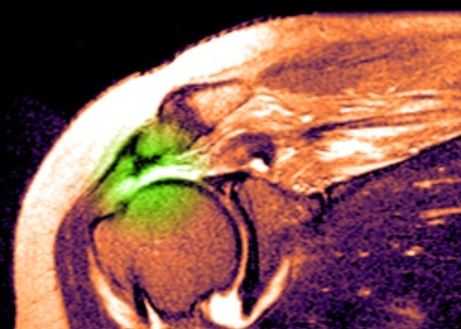

Травма плечевого сустава

МРТ плечевого сустава. Т2-взвешенная корональная МРТ. Разрыв вращательной манжеты. Цветовая обработка изображения.

Разрыв вращательной манжеты - также характерное повреждение области плеча - может быть связан как с травмой, так и дегенеративными процессами. Разрывы вращательной манжеты бывают полные и неполные. Кроме того, по МРТ плечевого сустава выделяют 3 градации, в основе которых лежит не только изменение сигнала на Т2-зависимых томограммах, но и морфологические изменения сухожилия.

При МРТ плечевого сустава косвенным признаком разрыва вращательной манжеты служит высокий сигнал на Т2-взвешенных от поверхности сустава до субакромиальной (субдельтовидной) сумки. Частичные разрывы чаще всего по передней поверхности сухожилия м.supraspinatus, реже примыкая к большой бугристости или сухожилия м. infraspinatus.

МРТ плечевого сустава. Т2-взвешенная корональная МРТ. Субакромиальное скопление жидкости - косвенный признак разрыва вращательной манжеты.

МРТ плечевого сустава. Т1-взвешенная корональная МРТ. Частичный разрыв вращательной манжеты.

МРТ плечевого сустава. Т2-взвешенная корональная МРТ. Передний разрыв вращательной манжеты